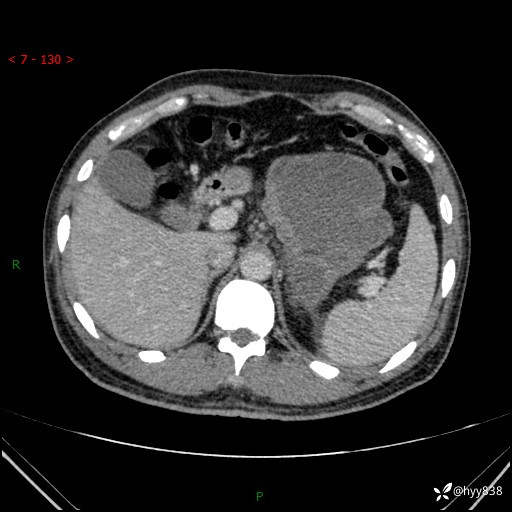

病例39岁/女,左侧腰痛入院。腹腔囊实性肿块,定位、定性---结果公布~

性别:男

年龄:39岁

简要病史:左侧腰痛待查,CT发现腹腔占位

腹部CT平扫+增强